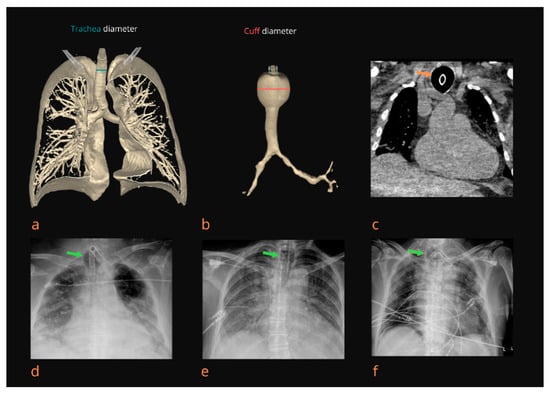

Figure 1.

Radiological diagnosis of tracheomegaly (TM). A 3D view (CT scan) of the tracheobronchial tree with determination of the diameter of the trachea (T diameter) in the clavicular area (a). A 3D view (CT scan) of the trachea with TM and determination of the diameter of the trachea in the cuff area (C diameter) (b). Native CT scan of the thorax thirteen days after intubation. A coronal plane showing TM in the cuff area (orange arrow) with a C/T diameter ratio of 2.31 (c). Chest X-ray shows TM (green arrow) in the area of the tracheostomy tube cuff nine days after intubation with a C/T diameter ratio of 2.12 (d). Chest X-ray shows TM (green arrow) in the cuff area of the endotracheal tube 8 days after intubation with a C/T diameter ratio of 1.95 (e). TM (green arrow) visible on a chest X-ray twelve days after intubation and three days after a tracheotomy with a C/T diameter ratio of 2.02 (f).